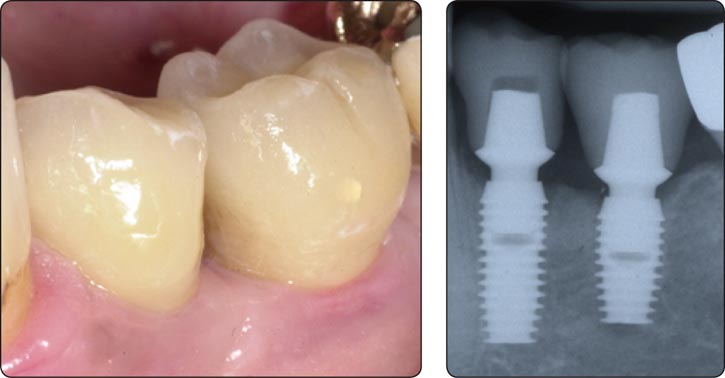

使用Bicon系统很容易获得牙龈美学的修复体-特别是Bicon 一体化基台冠(IAC)的出现。您再也不用因为黑色的龈染线道歉了。